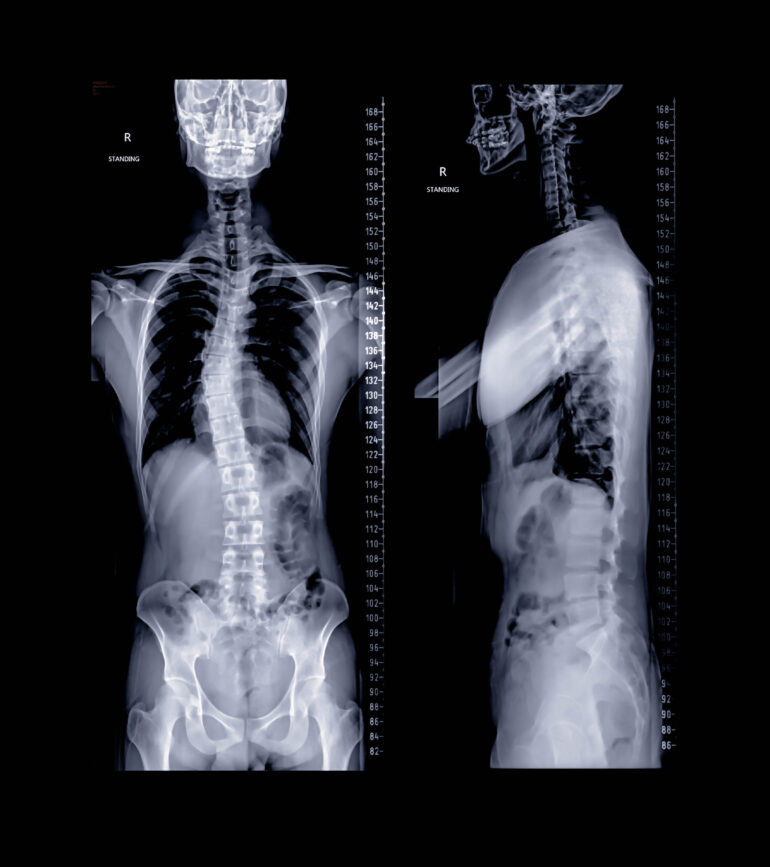

当院ではレントゲンとCT検査とMRI検査をします。当院の画像検査機器はこちらです。

まずはレントゲンで首から股関節までを一度に撮影して全体のバランスを見ます。全体を見ることで曲がり具合などが評価できます。

CT検査で骨がどのような形をしているか、どの程度ねじれているかなどの評価をいたします。手術する場合は背骨の中にネジを入れるので、入れるネジの太さや長さを調べます。

MR検査では神経の評価をいたします。ヘルニアや脊柱管狭窄など、他の病気がないかを調べます。